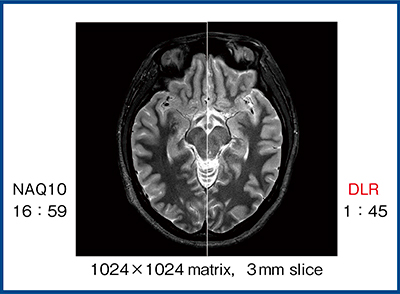

図2は,1024×1024マトリックス,3mmスライス厚のPD STIR画像である。フィルタ処理の場合,1回加算(NAQ1)ではSNRが低く,10回加算(NAQ10)では高SNRでコントラストも良好であるが,撮像時間は約17分を要する(図2 左)。一方,10回加算の画像を教師としてDLR処理を行うと,わずか1分45秒の撮像で10回加算の画像と同等の画質が得られる(図2 右)。

図2 PD STIR画像における10回加算とDLRの比較(W.I.P.)